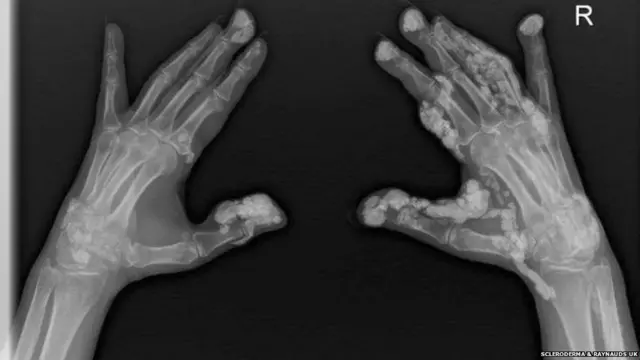

பட மூலாதாரம், SCLERODERMA & RAYNAUDS UK

- உடலின் ஆரோக்கியமான திசுக்களை பாதிக்கும் ஸ்கெலெரொடெர்மா குணப்படுத்த முடியாத நோய். தோல் பகுதியை நெகிழ்வுத்தன்மையை இழந்து முரட்டுதனமாக மாற்றுகிறது, இதுவே நோய்க்கான முதல் அறிகுறி.

- அதிக அளவிலான கொலாஜனை உருவாக்கும் இந்த நோய், உடலின் மூட்டுகள் மற்றும் உட்புற பாகங்களை பாதித்து, பாதிக்கப்பட்டவர்களை பலவீனமாக்கும்.

- குளிர்காலத்தில் கை மற்றும் கால் விரல்கள் வெண்மையாக மாறத் தொடங்கி பிறகு கடினமானதாகிவிடும்.

- ஸ்க்லெரோடெர்மாவின் ஒரு வகையான 'சிஸ்டமிக் ஸ்கெலெரோசிஸ்', உடலின் உட்பகுதிகளை குறிப்பாக நுரையீரலில் பாதிப்பை ஏற்படுத்தும்.